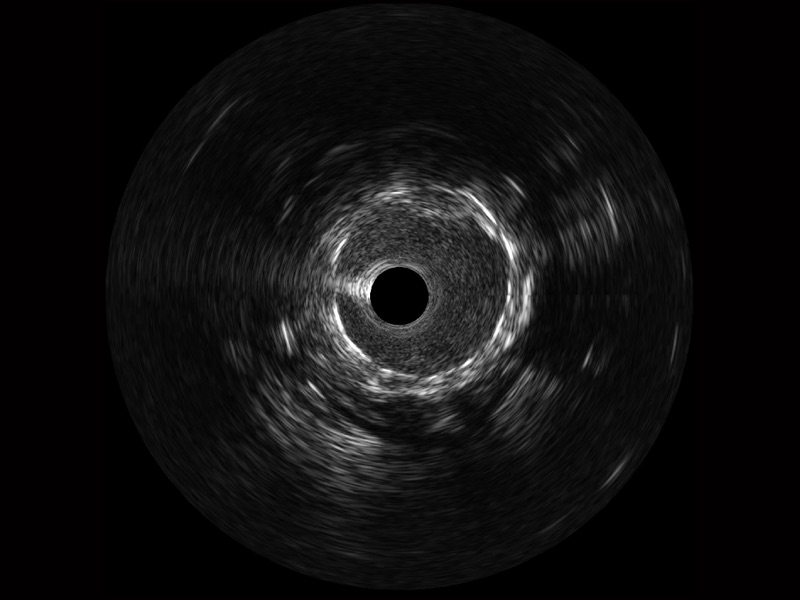

db真人体育官网宽频IVUS图像

对比传统IVUS导管成像,db真人体育官网宽频IVUS图像的近场支架梁显影更细腻,远场中膜外血管仍清晰可辨,兼顾远中近,兼顾分辨力与穿透深度